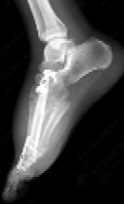

手术当天,麻醉手术部阳婷婷医生凭借丰富临床经验,顺利完成椎管内麻醉。在韩学哲与边卫国教授的指导下,杨卫周与刘俭涛医生精准切除受累的第一跖骨与内侧楔骨,并与整形外科何林医生顺利切取长约11厘米的小腿处带血管蒂腓骨,再通过“移花接木”式技术,将其移植至脚趾缺损部位。通过精细的显微外科技术,团队成功吻合足背血管,恢复移植骨块血运。在多科室通力协作下,手术圆满完成。

术后,在骨科护理团队的精心照护下,Adnan恢复良好,已于近日康复出院并顺利返回孟加拉国。